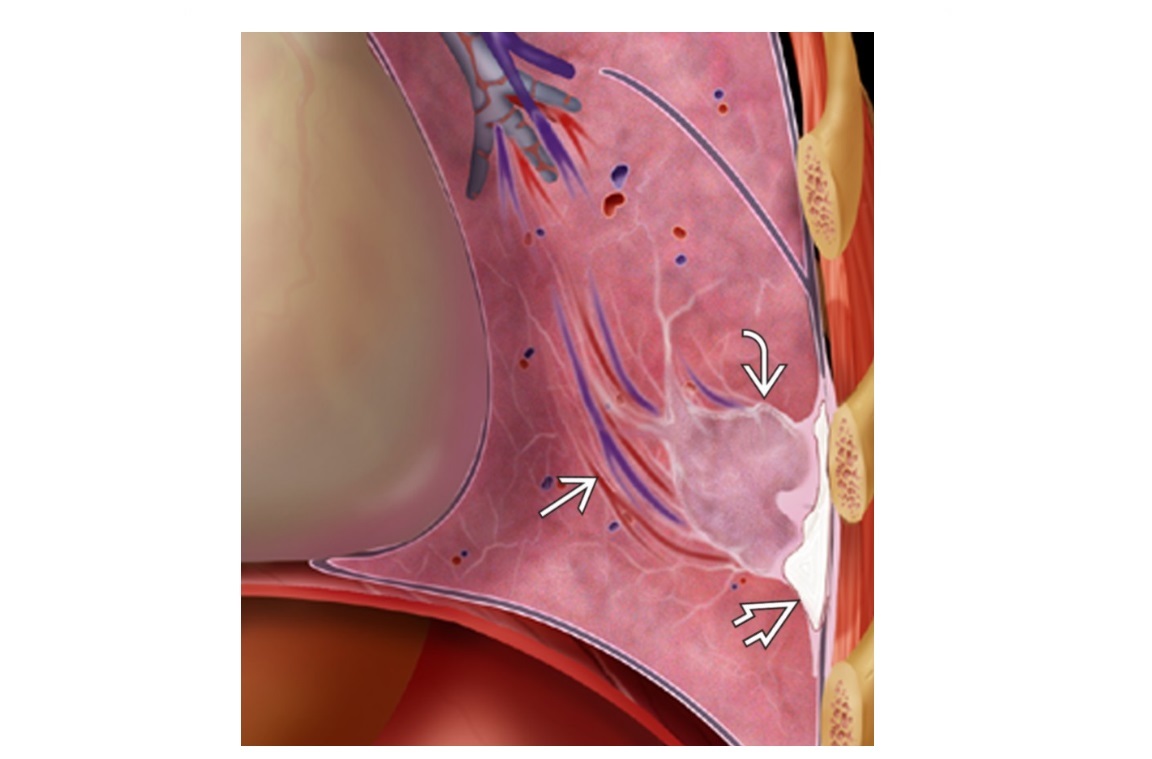

Round atelectasis

Comet tail sign

Adjacent to thickened pleural (assoacited with asbestosis) +/- Ca2+

can mimic a lung mass